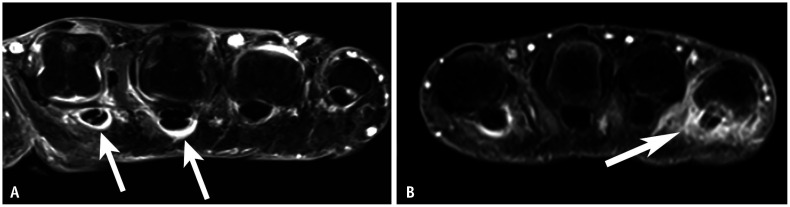

Tenosynovitis occurs in tendons with a tendon sheath, while inflammation around tendons without a sheath is typically described as peritendinitis. In the hand, the flexor tendon has a sheath up to its attachment at the distal phalanx [27]. In RA, flexor tenosynovitis is a strong predictor of early RA [28] and can be observed as abnormal fluid signal or enhancement within the tendon sheath (Figs. 4B, 7A, 8). In PsA, the development of flexor tenosynovitis can be explained by functional enthesitis between the tendon sheath and pulleys [29]. In addition to typical tenosynovitis findings, inflammation can spread to the subcutaneous area in PsA due to pulley involvement (Figs. 7B, 9). In PsA, the thickness of the pulleys—particularly the A1 and A2 pulleys—is greater than in RA or control groups [29,30].

Fig. 9. Pulley inflammation in PsA. A: Axial dual-energy CT iodine map of the hand in an 82-year-old female with PsA shows enhancement consistent with pulley structures (arrows). B: Illustration of an axial image at the metacarpophalangeal joint. On the palmar side of the FT, a fibrous band known as the pulley anchors the tendons to the bone. This structure corresponds to the enhancement area observed in (A). PsA = psoriatic arthritis, FT = flexor tendons, JS = joint space, DTML = deep transverse metacarpal ligament.